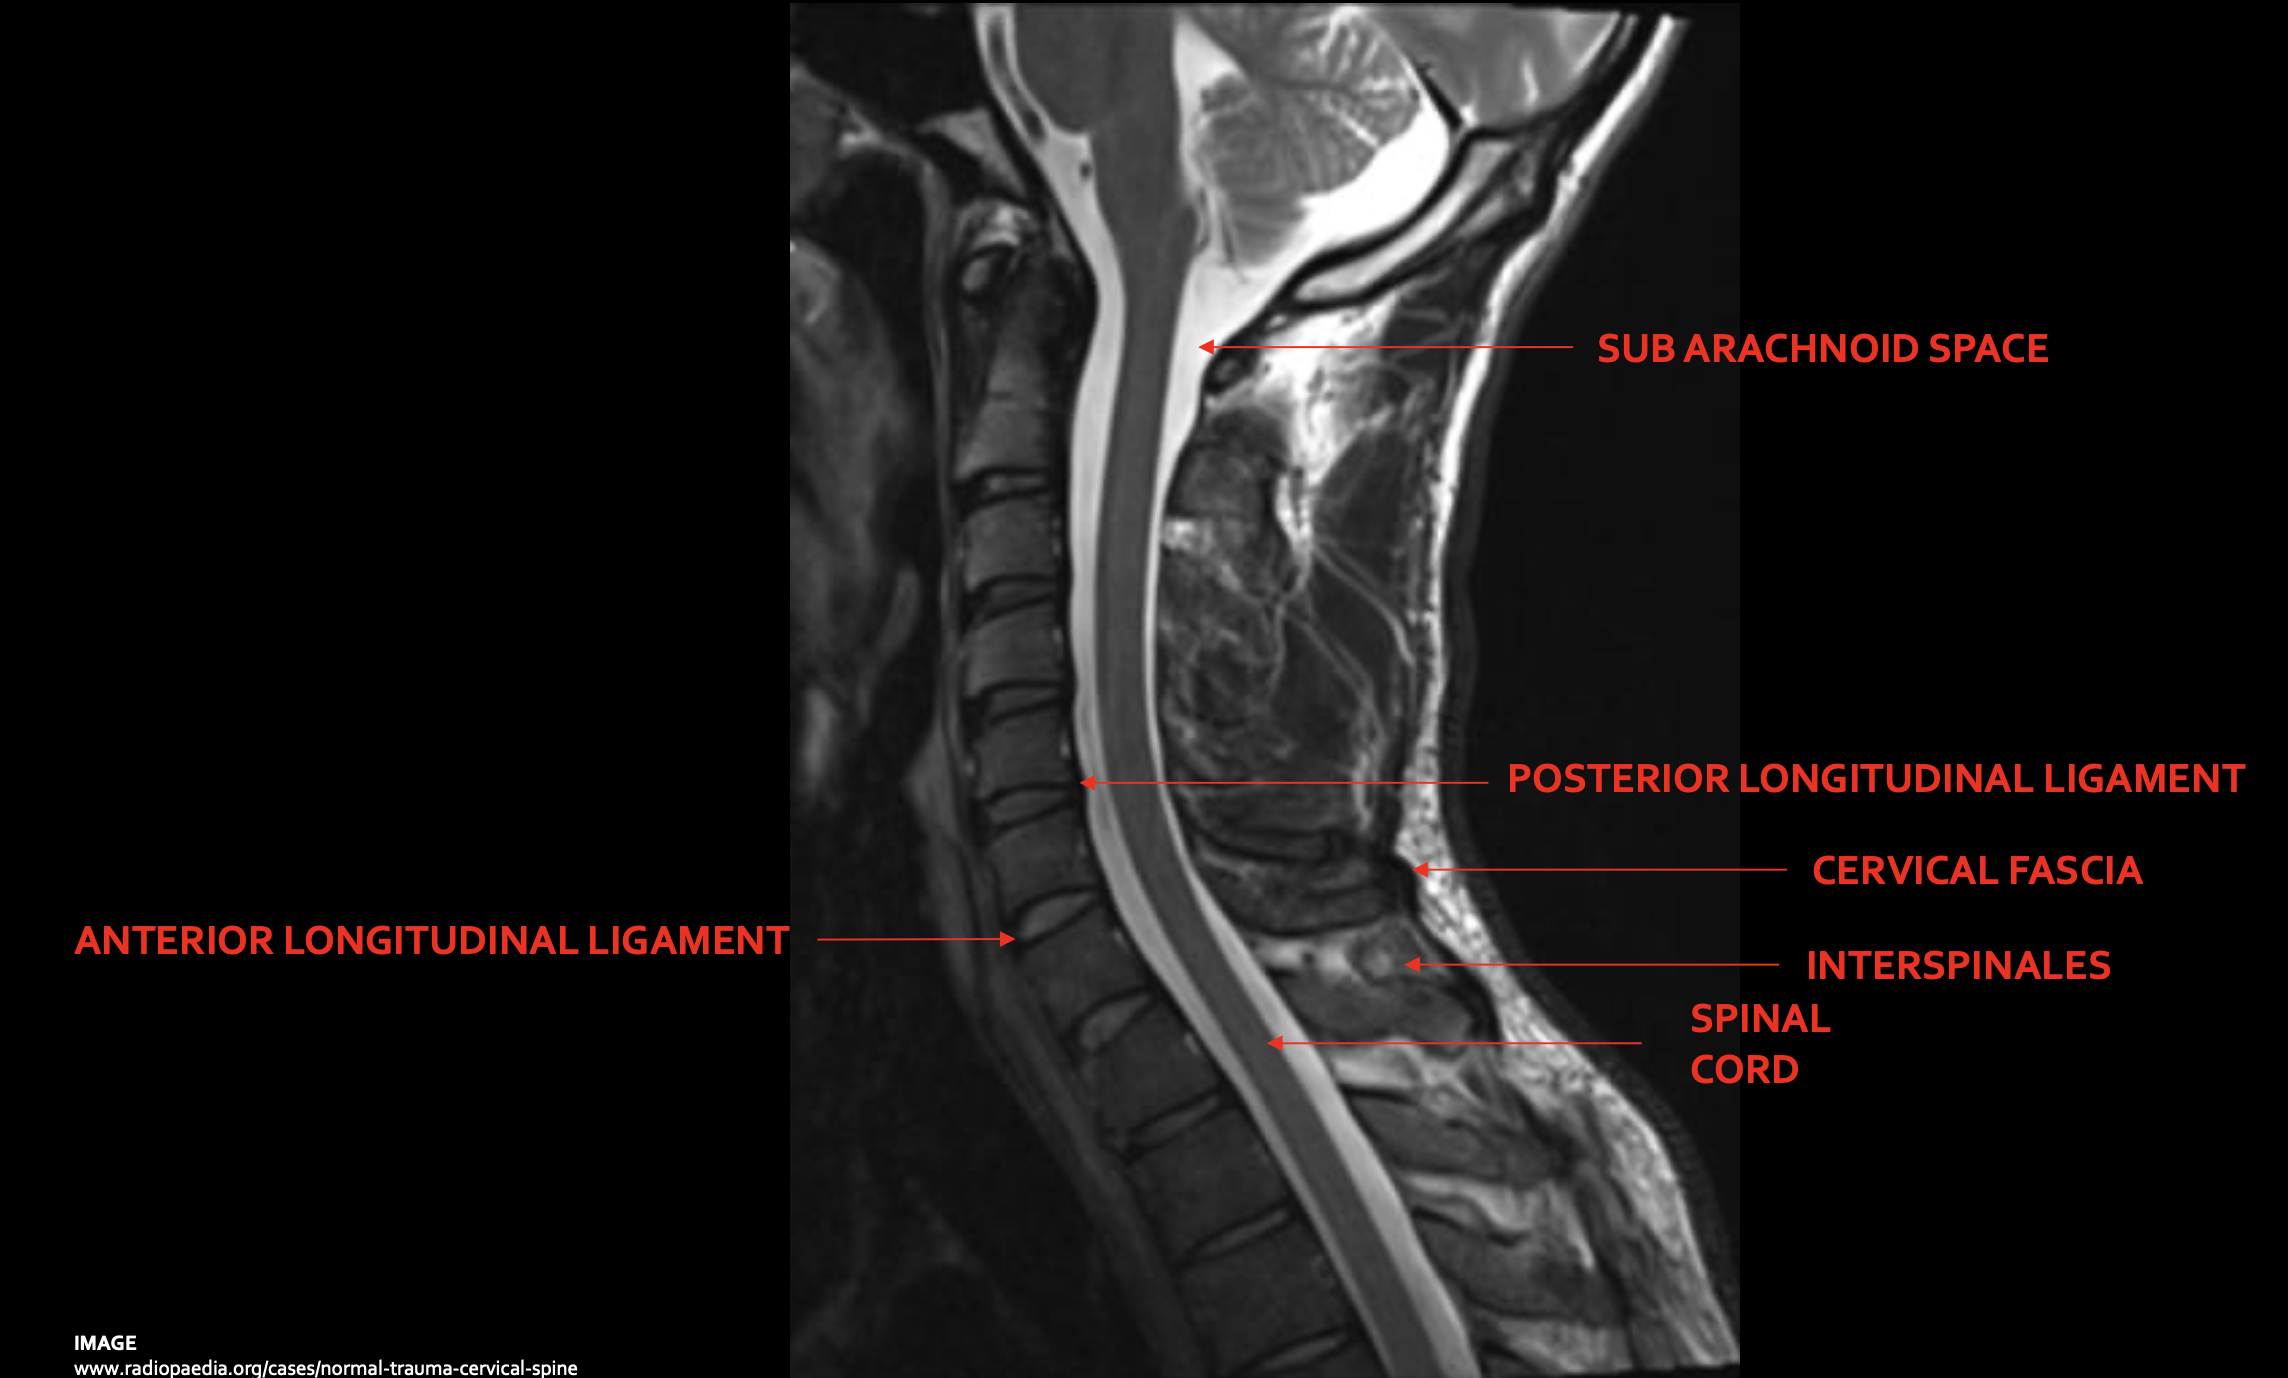

蛛网膜下腔

Subarachnoid space

脊髓

Spinal cord

前纵韧带

Anterior longitudinal ligament (ALL)

后纵韧带

Posterior longitudinal ligament (PLL)

颈深筋膜

Cervical fascia

棘间韧带

Interspinales